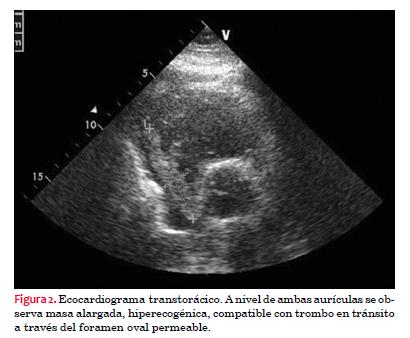

El ecocardiograma transtorácico reporta hipertrofia ventricular izquierda concéntrica de grado leve, función global y sectorial conservada, abombamiento del septum interventricular hacia ventrículo izquierdo. Dilatación del ventrículo derecho e hipofunción del mismo. Válvula aórtica esclerosada, resto de las válvulas estructural y funcionalmente normales. A nivel de ambas aurículas se observa masa alargada, hiperecogénica muy móvil que a nivel de la aurícula derecha mide 68 por 15 mm, que excede el plano de la válvula tricúspide y en aurícula izquierda mide 27 por 17 mm, compatible con trombo en transito a través de foramen oval permeable (FOP); vena cava normal, no ocupada. Elementos sugestivos de hipertensión arterial pulmonar leve (figura 2).